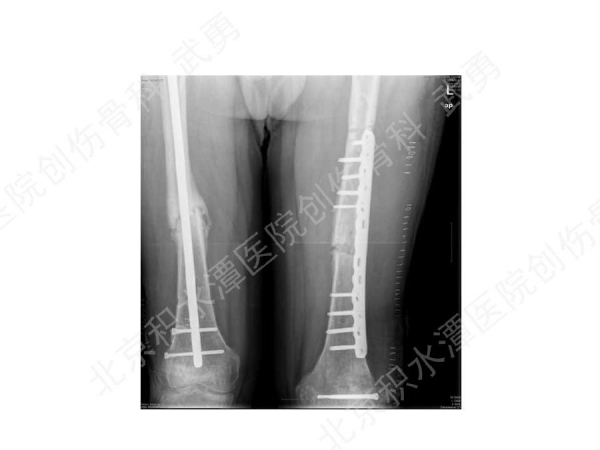

髓内钉骨不连的类型:增生型、萎缩型

髓内钉骨不连的治疗:

有关畸形愈合:

主要发生在干骺端, 髓腔增宽,无法控制稳定(成角)

解决办法:阻挡钉技术(Poller screw)等